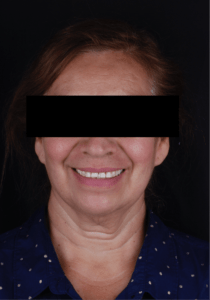

Paciente femenino de 57 años, ama de casa, originaria de Arandas, Jalisco se presenta al departamento de Periodoncia e Implantología derivada por el departamento de Prostodoncia. El motivo de su consulta fue “Quiero reponer mis dientes restantes” como resultado de la anamnesis presenta un buen estado de salud general aparente, sin antecedentes patológicos. (Fig. 1).

Fig. 1